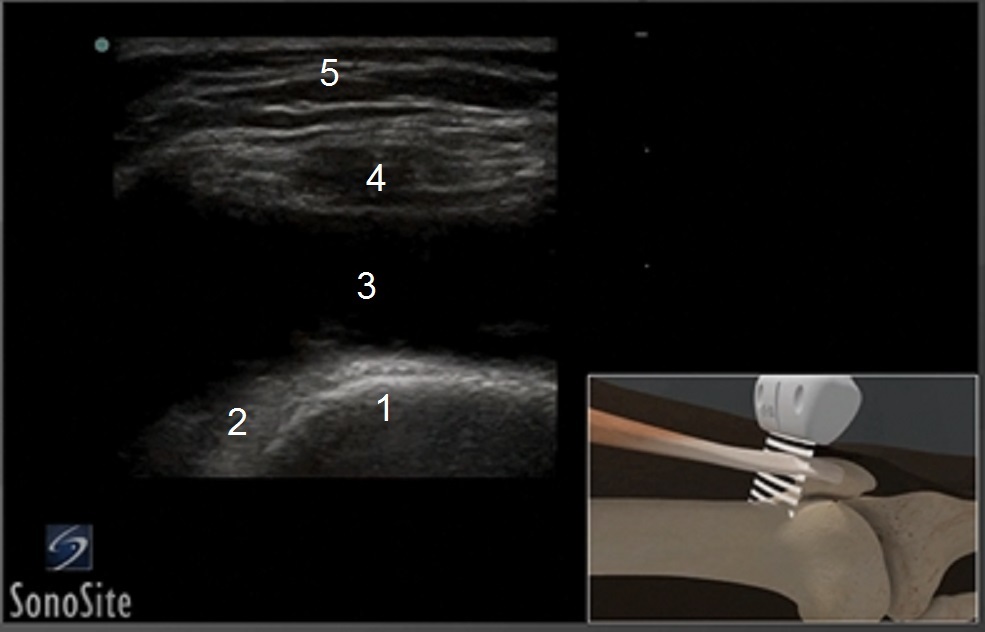

Anatomie des Knies Bild 3

1. Femur

2. Präfemoraler Fettkörper

3. Gelenkerguss

4. Sehne d. Quadrizeps

5. Subkutanes Fett